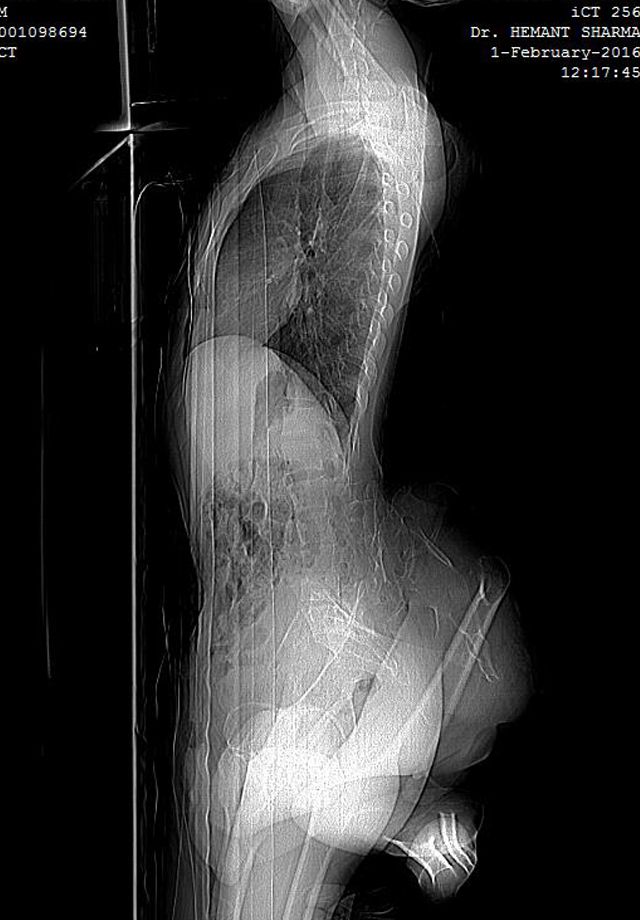

Молодой индиец с четырьмя ногами просит врачей избавить его от лишних конечностей